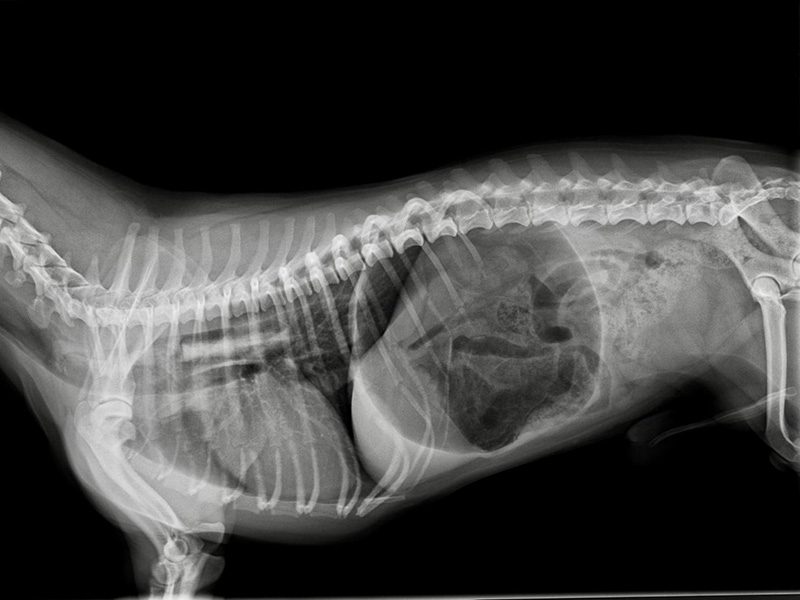

Digitales Röntgen

In unserer Praxis bieten wir eine technisch ausgereifte, schnelle digitale Strahlendiagnostik, die durch eine hohe Bildqualität und eine digitale Bildbearbeitung optimiert wird. Dadurch wird >>> weiterlesen